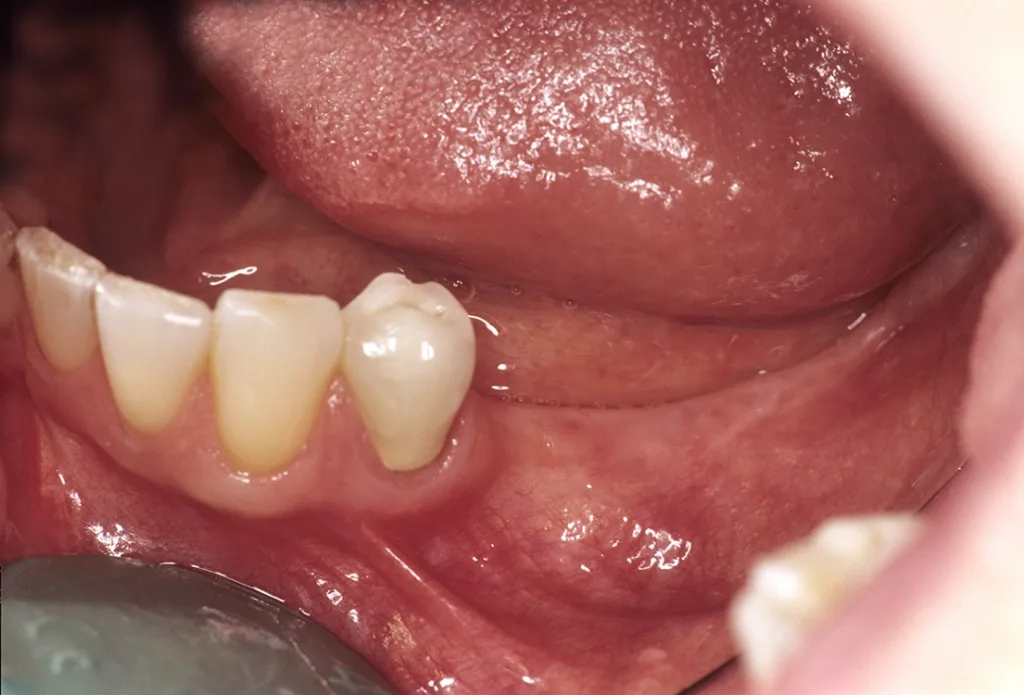

- Bei ortsständiger Implantation Verbreiterung der periimplantären Gingiva durch leicht oralwärts verlagerte Inzision (reicht meist aus).

- Bei lateraler Augmentation ist eine Verbreiterung aufgrund der Lappenmobilisation zur Defektdeckung absehbar. In der Einheilungsphase vor Freilegung separater Behandlungstermin mit Vestibulumplastik und freier Schleimhauttransplantation (Gaumen) (Abb. 17 bis 19).

- In Einzelfällen und bei Zahnlosigkeit im Unterkiefer Verbreiterung durch Edlan-Mejchar-Vestibulumplastik mit Schaffung einer attached Mukosa als gestielte Lappenplastik mit gutem ästhetischem Resultat vor Implantation. Sie kann auch zur Kompensation nach Implantation erfolgen (Abb. 20 bis 22).